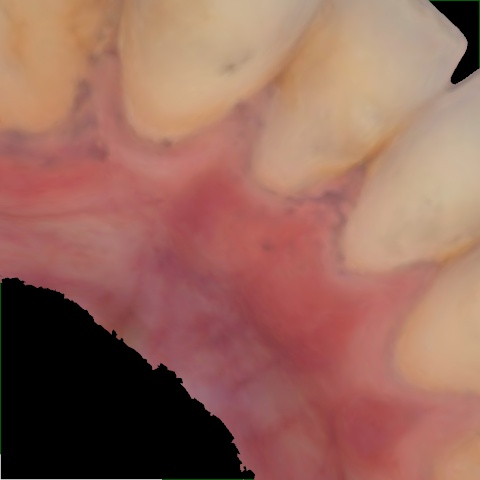

Annotated as "Bad"